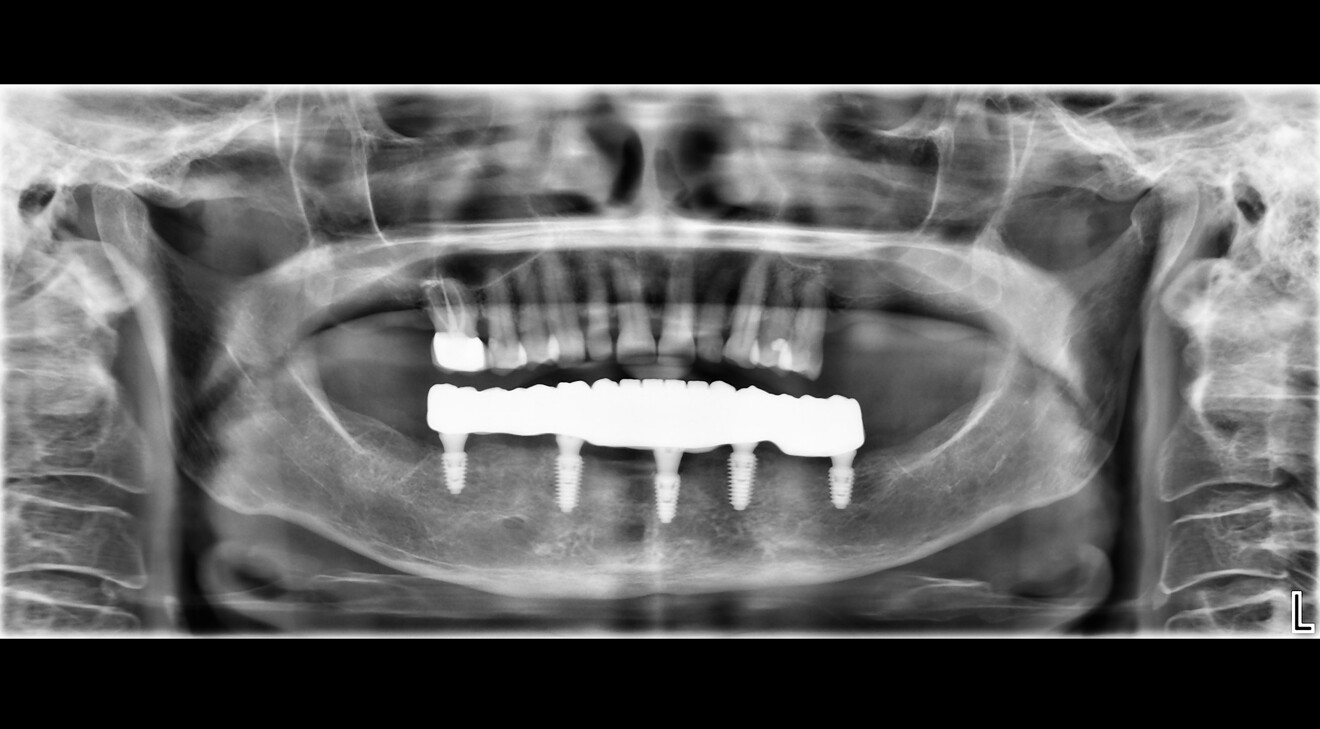

Fig. 7: Panoramic radiograph for scan body verification.